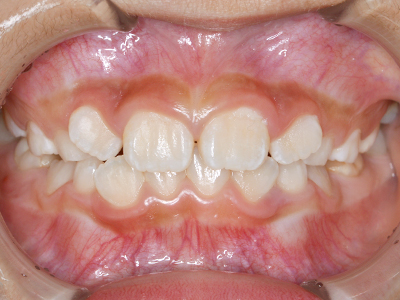

歯並びの相談に来られるお子様は、口呼吸をしているケースが多く、これが歯並びに大きな影響を与えています。

- 口呼吸をしている

↓ - 舌の位置が悪くなる

↓ - 頬の圧力が上の歯列にかかりやすくなる

↓ - 上あごが狭くなる

↓ - 下あごが狭くなる・下あごの位置が悪くなる

↓ - さまざまな不正咬合が生じる

ないき歯科クリニックでは、上あごの成長不足を補い、鼻呼吸を獲得しつつ歯列を整え、将来のお口をより健康な状態にすることをゴールに定める矯正治療をおこなっています。